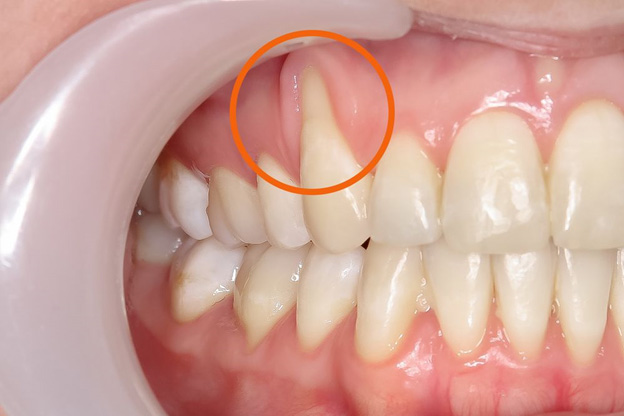

Gum recession is a common dental problem where the gum tissue pulls away from the teeth, exposing the roots. This can lead to tooth sensitivity, increased risk of decay, and even tooth loss if left untreated.

- Exposed Tooth Roots

- Gums Appearing Thinner or Pulled Back

Gum recession denotes gum disease where the gum tissue withdraws from the teeth, uncovering the roots beneath. It increases the susceptibility of teeth to cavities and can lead to heightened tooth sensitivity during brushing and eating. One or multiple teeth may be involved. While gum recession can impact individuals of all age groups, it is more common in people over 65.

Visible Tooth Roots: One of the primary signs is the exposure of tooth roots as the gum line recedes

Longer Teeth: Teeth may appear longer than usual due to the recession of the gums.

- Misalignment of tooth structure.